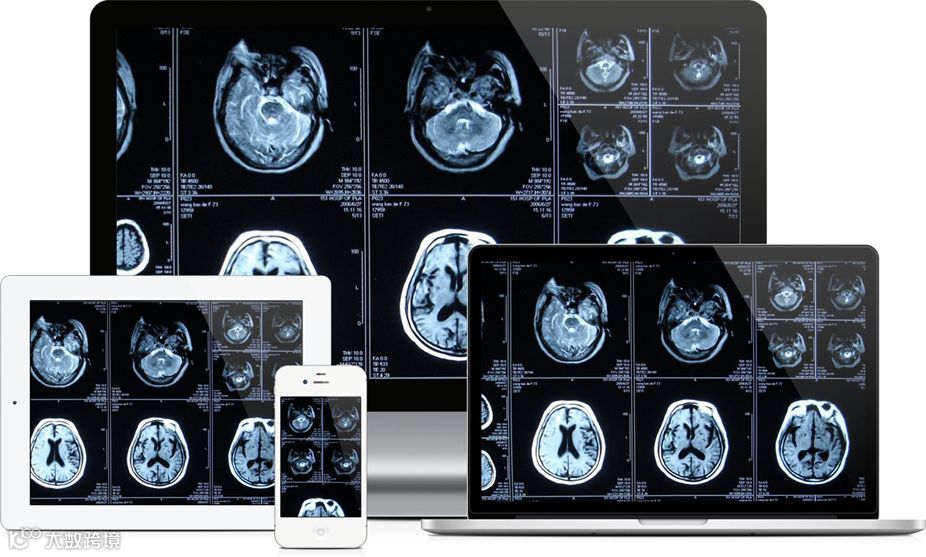

目前全球大部分医疗机构的医学影像系统(PACS)采用的都是DICOM(Digital Imaging and Communications in Medicine)标准。但是由于医院系统之间的封闭性和异构性,医学影像数据隔阂和孤岛问题仍然严重,这不仅阻碍医学影像数据的共享以及个人医学影像电子健康档案的建立,也对构建基于医学影像的智慧医疗服务增加了困难。建立医学影像区域云,显然可以解决影像数据多地域存储、跨地区数据备份的问题,实现区域影像共享。数据的云端共享,打破了医院信息的“孤岛”,影像医生可以不受时间、地点的束缚,随时随地在移动端对原始DICOM影像数据进行查阅、诊断。

云能让影像医生多终端浏览DICOM数据